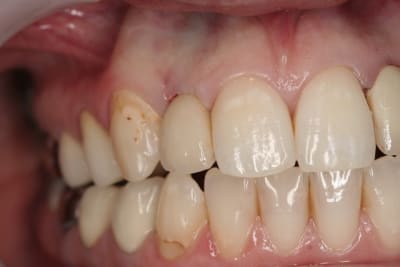

photos finish!!!

à noter...avec le flash...difficile de rendre le "naturel" de ces restaurations(teintes très claires)...après petite gingivoplastie pour harmoniser la hauteur des collets...(surtout pour 12...)